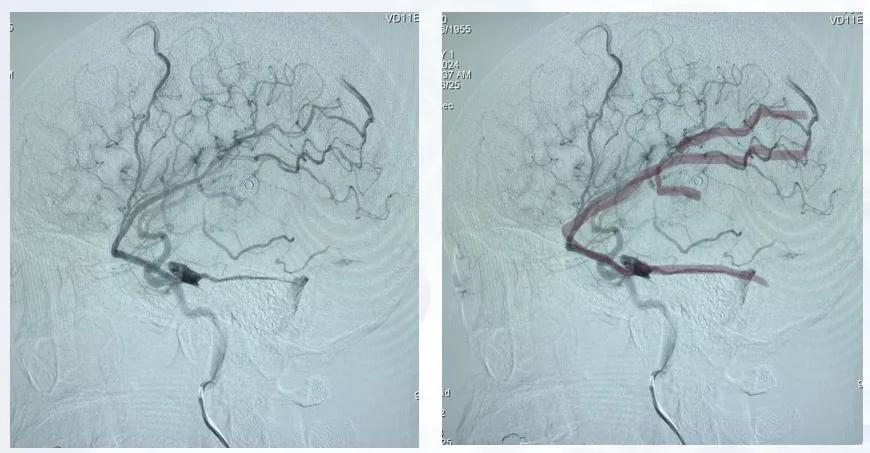

治疗策略:采取“动脉瘤栓塞+畸形团介入栓塞+开颅畸形团切除”的联合治疗。因右侧动脉瘤与畸形团位置较远,术中定位困难,先对右侧动脉瘤行介入栓塞,以降低再出血风险;随后对畸形团行部分栓塞,控制血流;再行开颅手术切除右侧主要畸形团。左侧其余未处理的畸形因体积较小、位置深在,建议后续行放疗,进一步控制病变,避免远期再出血风险。术后因颅内压较高行去骨瓣减压。

预后:术后患者神志清楚,颅内情况稳定,术前肢体瘫痪症状明显改善,下肢肌力恢复至2~3级,上肢肌力1~2级。术后1个月复查脑血管造影,显示右侧畸形团已切除,未见残留显影。患者后续仍需定期随访与康复训练。

图10 患者术后复查血管造影